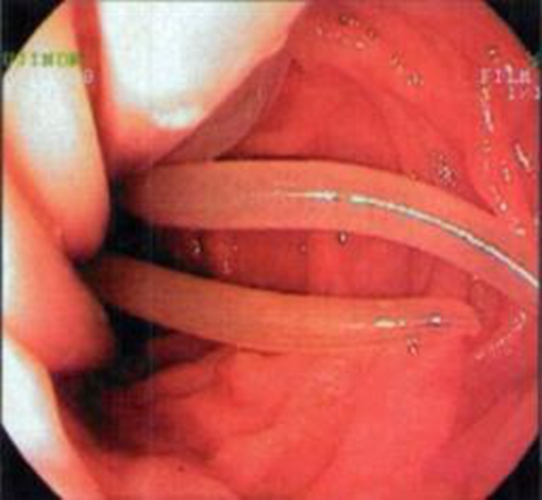

腸絛蟲病圖片

A:腸絛蟲病以大便常規檢測,見到有排出的絛蟲節片為主要診斷依據。常見的有豬帶絛蟲病和牛帶絛蟲病,主要是因為進食了含有囊蚴的豬肉或者牛肉而出現感染。治療方面主要是驅蟲治療,比如說用吡喹酮。一般情況不需要導瀉療效都可以達到95%以上。另外可以口服甲……

A:絛蟲病是因為各種成蟲寄生在人體的小腸而引起的疾病的總稱。比較常見的有豬帶絛蟲病和牛帶絛蟲病。主要是因為進食了含有囊蚴的豬肉或者牛肉而出現感染。它的潛伏期比較長,一般要需要幾周的時間。患者通常沒有什麼明顯的不適,一般是在大便中發現白色帶狀節片……